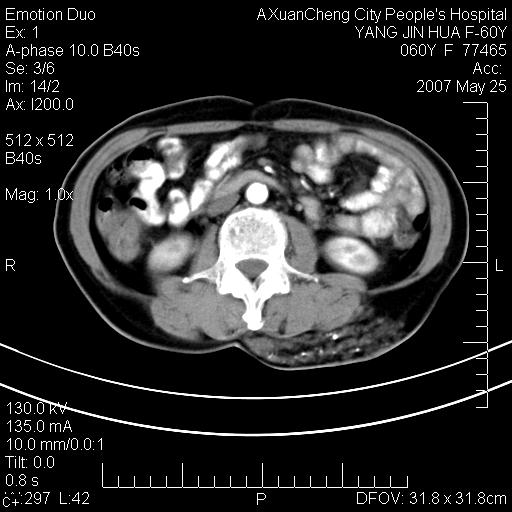

发现左侧腰背部包块40余年,逐渐长大,质软,局部表面可见扩张的血管影

左背部皮下良性肿瘤,密度不均,边界不清,内有脂肪、钙化,增强扫描无明显强化,血管平滑肌脂肪瘤?进一步诊断有困难,建议穿刺活检。

左侧背部皮下混杂密度肿块,结构较疏松,边缘欠光整,内有多发斑点状钙化,考虑:皮下血管瘤。

这个病理增强扫描之前,我们是考虑是血管瘤,可是现在增强后一点强化都没有,还能考虑是血管瘤吗